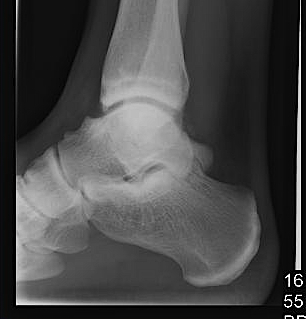

• Background